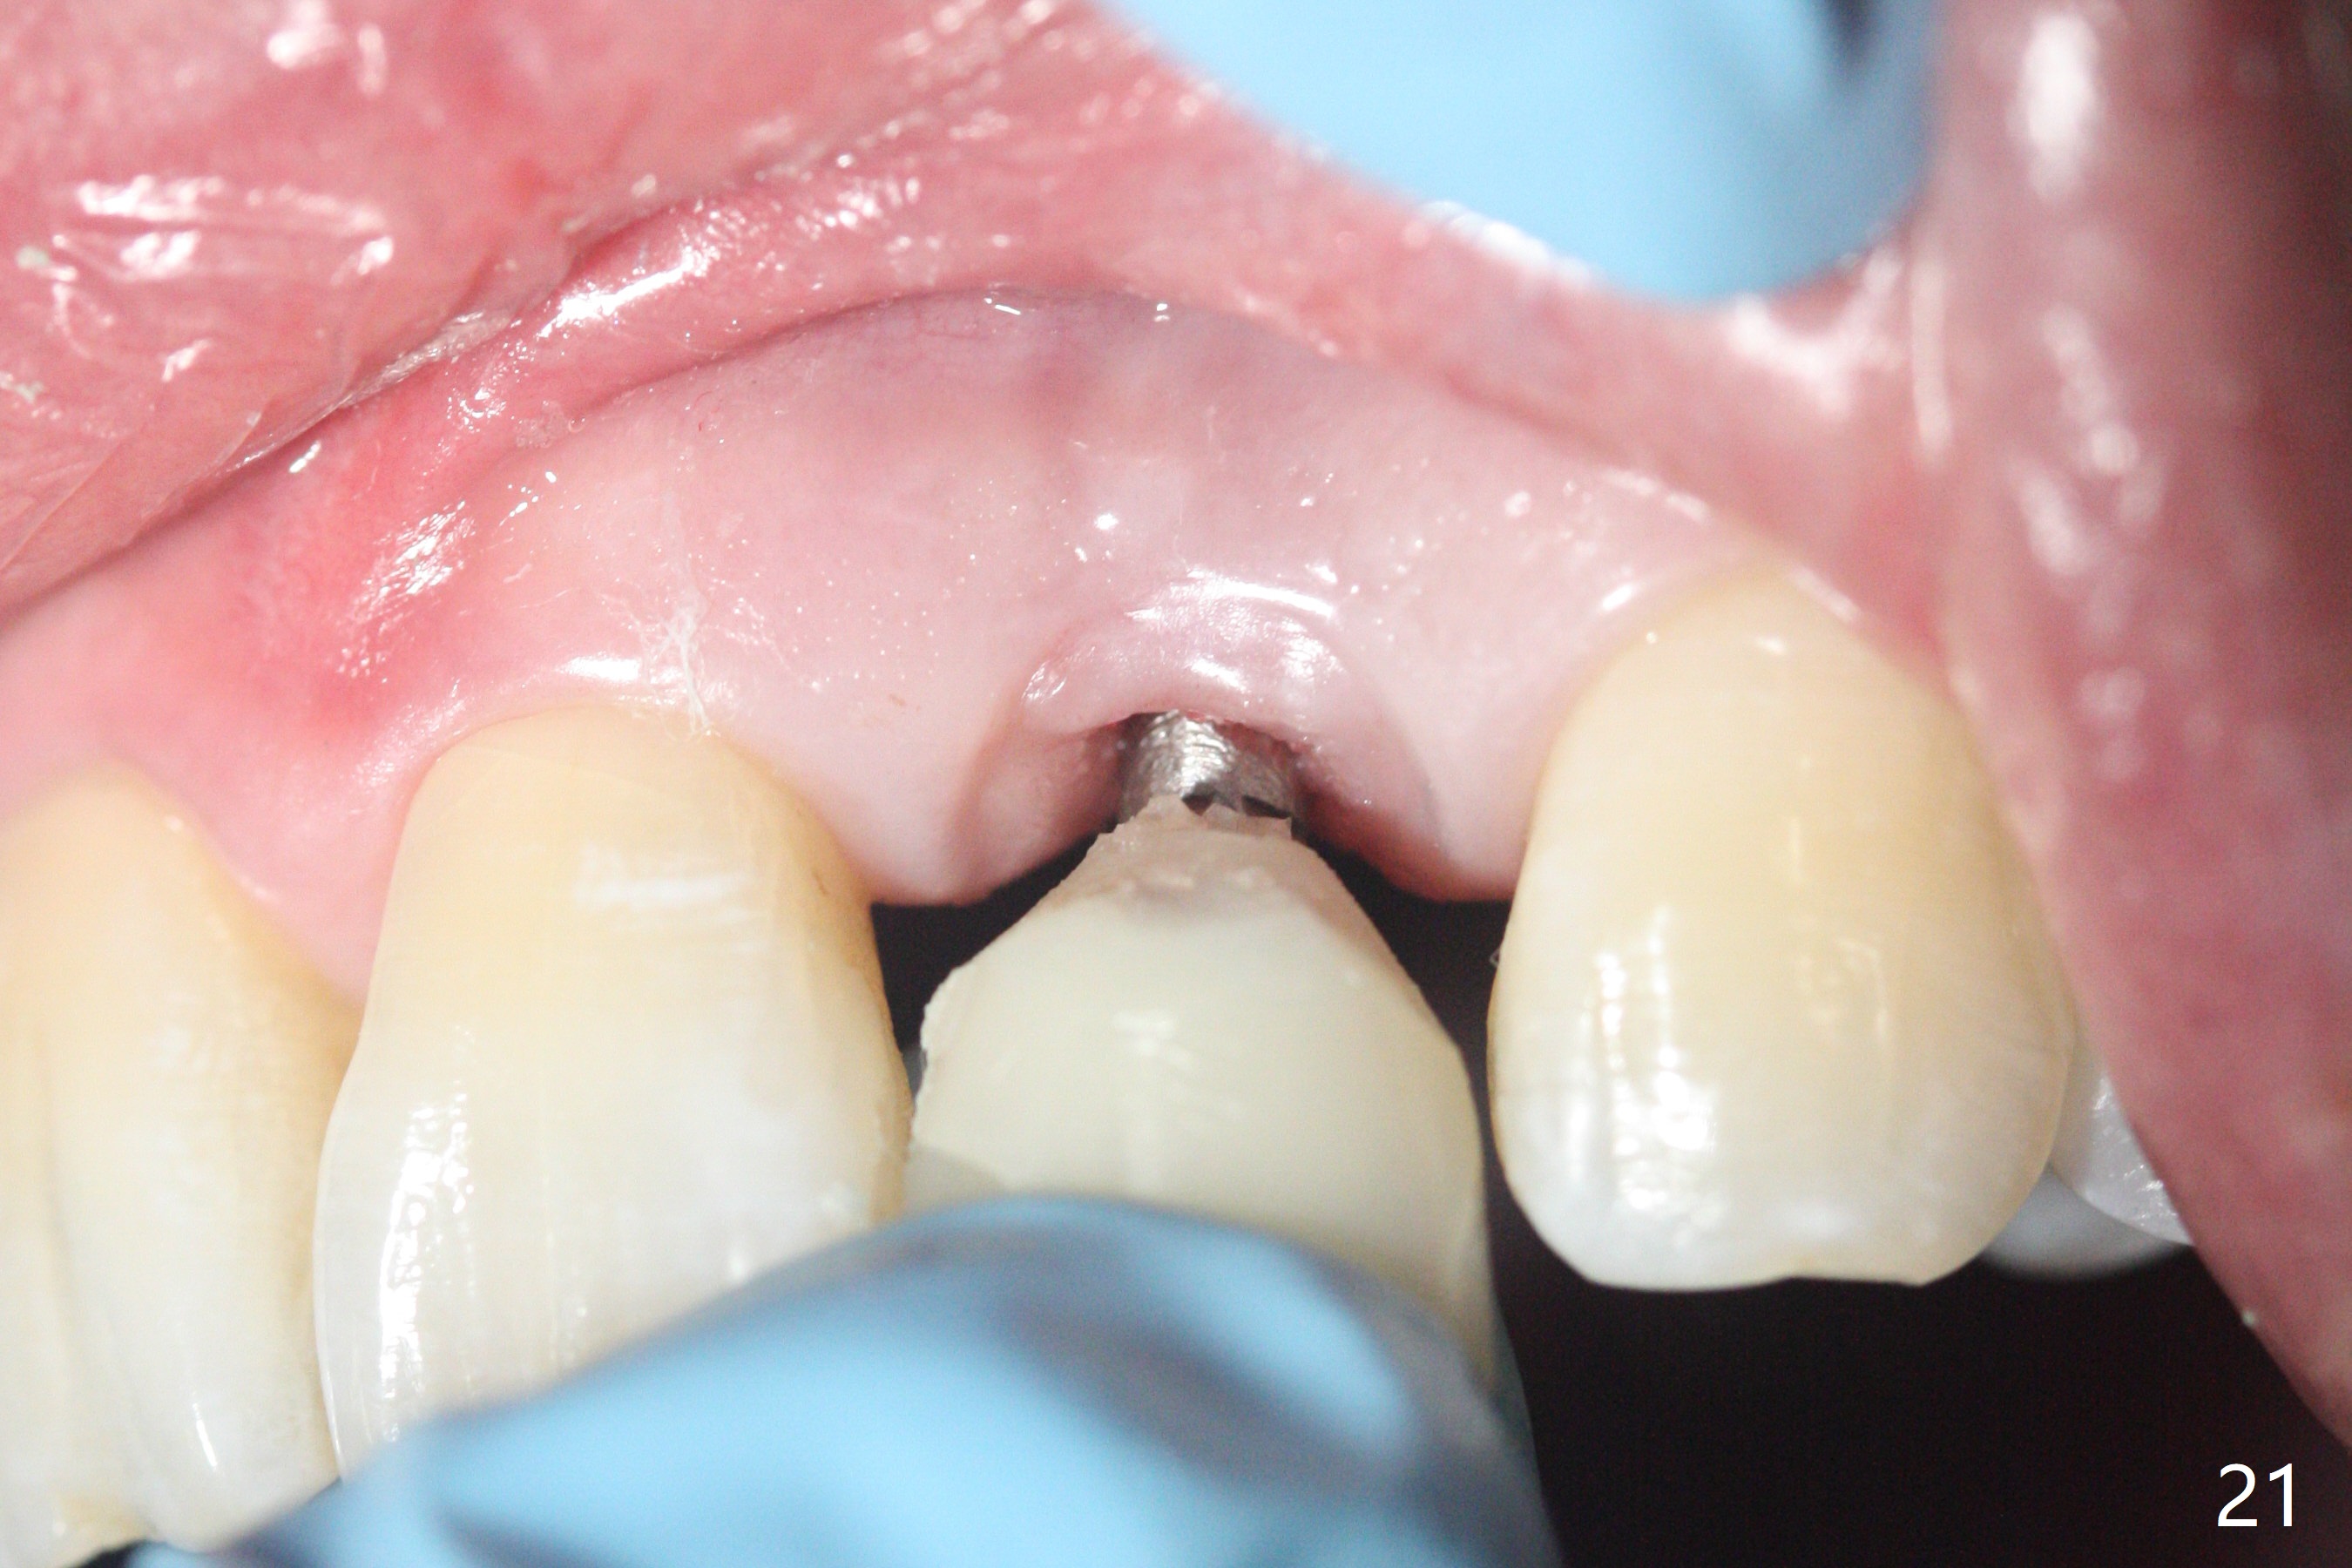

病人回来带来瘘道(图一),不过不会增加难度,病牙去除,它便自动消失。尽管颊侧骨壁完全失去,颊侧牙龈仍丰满(图二),为什么呢?第一,因为粗大牙根存在,第二两旁牙齿,牙槽骨撑着帐篷(侧切牙颊侧牙龈),第三,牙冠。为了防止术后牙龈塌陷,尽量不切开,即刻放置植体(牙根);由于前牙缘故,这次植体不能很大,所以植骨必须过度(over grafting),最后即刻制作临时牙冠,撑住牙龈。这就是所谓每个人进入角色。这个牙根有一种先天性畸形:dens in dent (图三(腭侧观):箭头)。尽管腭侧牙根畸形,腭侧骨壁吸收临床上并不严重,所以钻洞仍偏腭侧。当预定最后钻头还在钻洞时,填入大量粘性骨块(图四:*),细长植体还没有完全卡入鼻底(图五),最后好像可以(图六,七)。植体,骨粉入位(图八),最后临时牙冠出场(图九)。尽管植体小,术后一周临时牙冠仍然可以维持牙龈原有形状(emergency profile,图十:箭头(*:树脂强化牙冠固定))。图十一以不同角度显示瘘道缩小。术后三周取出有些松动的临时牙冠,骨粉虽然还没有被肉芽组织整合,但是显得正常,周围牙龈健康(图十二)。术后4个月牙龈形态正常(图十三),没有触痛;颊侧骨板轻度凹陷(图十四);骨粉仍在原位(图十五)。术后7个月骨粉仍在原位(图十五,十六,但是冠部密度减低(可能骨粉流失,需要牙周或者树脂敷料保护)),没有螺纹暴露。但是牙冠边缘暴露,说明牙龈收缩(图十七,与图十三对比),颊侧骨板仍塌陷(图十八)。插入龈线取得多个目的:修整基台边缘,取模,颊侧牙龈推向颊侧,有利于即将衬里牙冠龈缘进入龈下(图十九)。取模后牙冠边缘(图二十:<)衬里,然后修整,变窄,以便插入龈下,促进颊侧牙龈下降(图二十一,二十二)。术后8个月牙冠粘固前牙龈健康(图二十七,八),牙冠(图二十九)固位后,病人满意(图三十),咬合调整(图三十一),注意腭侧粘固粉流出通道(<)。